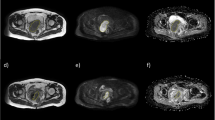

One radiologist (R1), board-certified with > 10 years’ experience in abdominopelvic MRI, manually drew volumes of interest (VOIs) using the freehand selection tool on ImageJ (ImageJ 1.52a, National Institutes of Health) to encompass the whole primary tumour on T2W images b1000 DWI images with reference to the T2W images and D parametric maps of pre- and post-CCRT images (Fig. 1). The radiologist was given both sets of images and was aware of the sequence of the MRI examinations. The T2W VOIs were used to measure tumour volume, while the DWI VOIs were then propagated to co-registered D and f parametric maps estimated with the full BVD and optimised subsample BVD (Fig. 2). The radiologist was also asked to measure the length of the tumour’s longest axis on T2W images for treatment response assessment.

Representative pre-concurrent chemoradiotherapy (pre-CCRT). a T2-weighted (T2W) images to aid in tumour delineation on. b Diffusion-weighted images (DWI), b = 1000 s/mm2. c Regions of interest were drawn by the senior radiologist to encompass the whole tumour area and was repeated on subsequent slices to include the entire tumour volume. The volumes of interest were propagated to co-registered pure diffusion coefficient (D) and perfusion (f) parametric maps. Tumour delineation was also done on post-CCRT images (d–f)

Representative pre-concurrent chemoradiotherapy (pre-CCRT). a Diffusion-weighted images (DWI), b = 1000 s/mm2 that were also overlaid with parametric maps of (b) pure diffusion coefficient (D) and (c) perfusion fraction (f) over the tumour as well as the corresponding (d–f) post-CCRT images and parametric maps. The cyan regions of interest (ROI) represent the first delineation by the senior radiologist on DWI which was copied to the D and f parametric maps